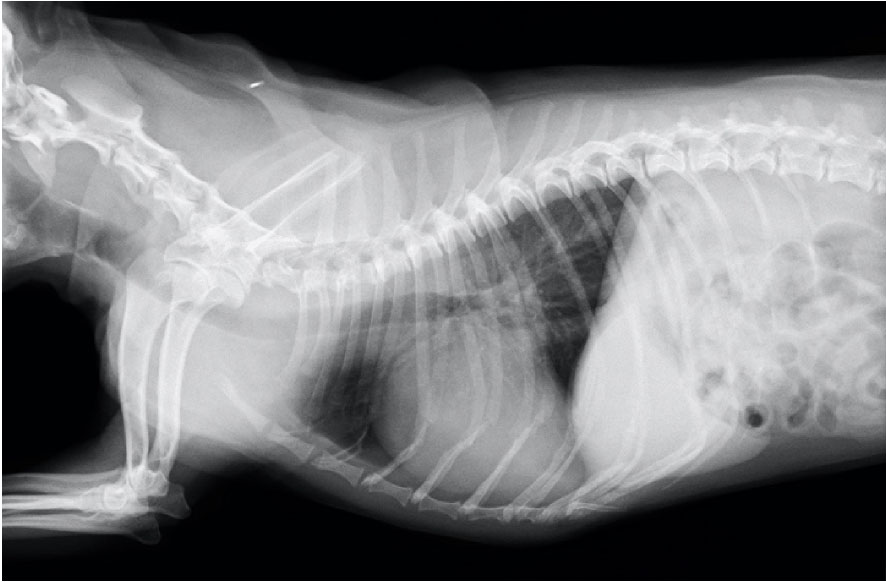

結紮後

| 犬種 | ミニチュアダックスフント 3ヶ月 2.7kg 雌 |

| 初診時の症状 | 軽度の咳と運動後に呼吸が速くなるとのことで来院。身体検査では、連続性雑音が聴取されたため,心臓エコー検査を実施。 動脈管開存症(左-右短絡)と診断しました。 |

| 治療と経過 | 左側第4肋間開胸による動脈管結紮術を実施し,術後は集中治療室で酸素管理や投薬治療を行いました。順調に回復し、呼吸状態も安定。退院後は活発に動きまわり,元気に生活しています。 |